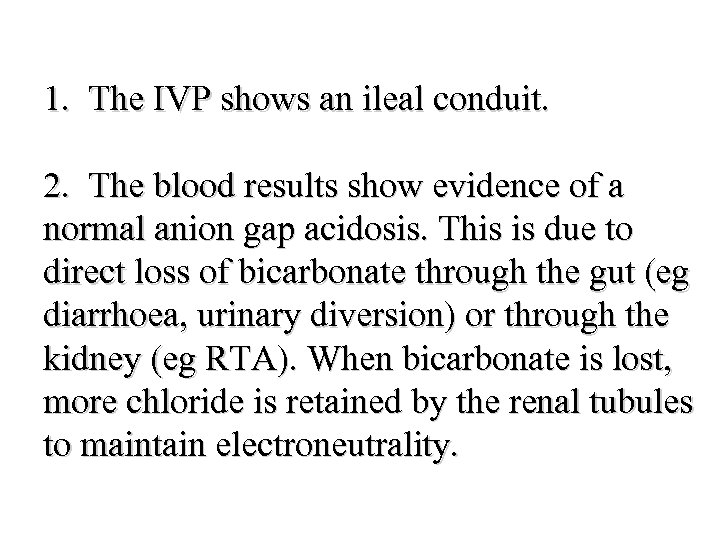

4. A 29 -year-old woman presents with weakness and is found to have a serum potassium of 2. 2 mmol/l and p. H 7. 1. Which of the following would be most suggestive of proximal renal tubular acidosis (RTA type 2)? • • • A B C D E Renal calculi Osteomalacia Serum bicarbonate 8 mmol/l Urinary p. H 6. 5 History of Sjogren’s syndrome

4. A 29 -year-old woman presents with weakness and is found to have a serum potassium of 2. 2 mmol/l and p. H 7. 1. Which of the following would be most suggestive of proximal renal tubular acidosis (RTA type 2)? • • • A B C D E Renal calculi Osteomalacia Serum bicarbonate 8 mmol/l Urinary p. H 6. 5 History of Sjogren’s syndrome

4. A 29 -year-old woman presents with weakness and is found to have a serum potassium of 2. 2 mmol/l and p. H 7. 1. Which of the following would be most suggestive of proximal renal tubular acidosis (RTA type 2)? • • • A B C D E Renal calculi Osteomalacia Serum bicarbonate 8 mmol/l Urinary p. H 6. 5 History of Sjogren’s syndrome

4. A 29 -year-old woman presents with weakness and is found to have a serum potassium of 2. 2 mmol/l and p. H 7. 1. Which of the following would be most suggestive of proximal renal tubular acidosis (RTA type 2)? • • • A B C D E Renal calculi Osteomalacia Serum bicarbonate 8 mmol/l Urinary p. H 6. 5 History of Sjogren’s syndrome